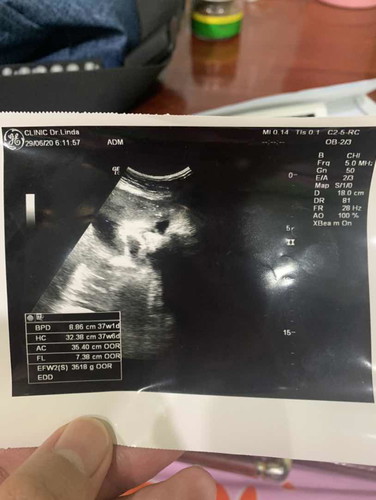

37w

เบบี๋ในท้องน้ำหนักเท่าไหร่กันแล้วคะ บ้านนี้ 3518 g แล้วน๊าาา